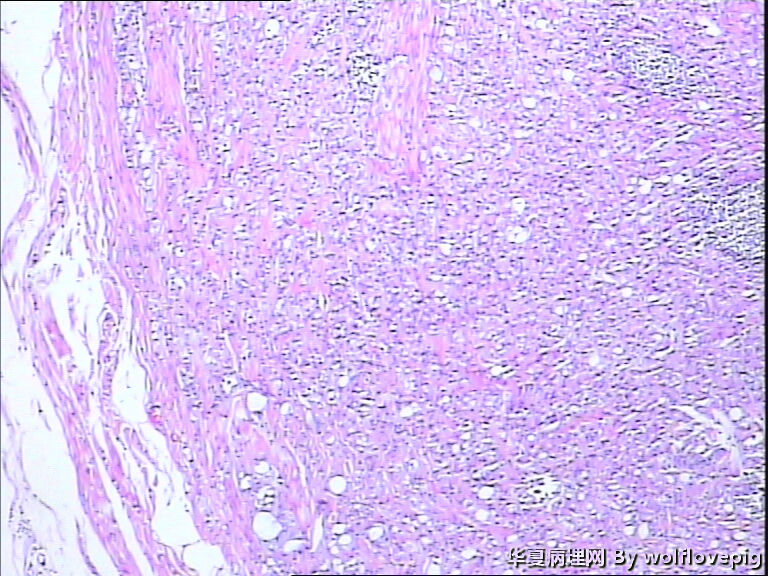

男,60y,左阴囊包块6月,位于附睾尾与睾丸之间,无粘连。灰白结节一个0.7*0.3*0.3,切面灰白、实体 、质韧。